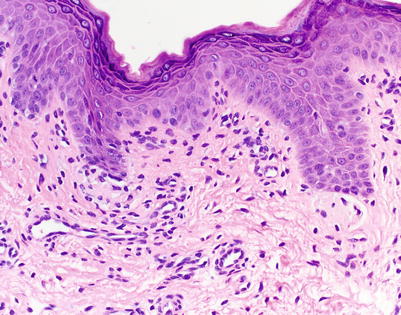

Fig. 5.1

Acute vacuolar interface dermatitis. Basal keratinocyte vacuolization is present, with cytotoxic lymphocytes aligned along the basal layer. Overtly necrotic keratinocytes are absent. These findings correspond to acute graft-versus-host disease (aGVHD) histologic grade I, changes considered insufficiently specific to make a definitive GVHD diagnosis (H&E-stained section, 200× magnification)